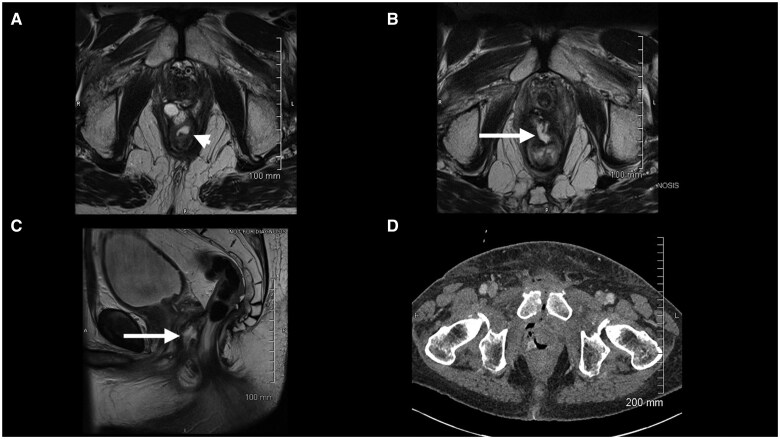

有盆腔放射史的前列腺癌患者的放射治疗可能受到直肠剂量限制和直肠毒性风险的限制。直肠间隔剂已被证明可以改善前列腺癌治疗中的直肠剂量学。本研究旨在评估先前接受过放射治疗的前列腺癌患者在直肠和前列腺之间放置水凝胶间隔物(特别是SpaceOAR)的安全性和结果。在这个回顾性的病例系列中,我们分析了8例连续接受盆腔放疗或盆腔放疗的患者的医疗记录,这些患者接受过经会阴SpaceOAR安置。我们记录了SpaceOAR放置后、放疗前后的并发症发生率。在这个患者队列中有一系列的并发症,从盆腔疼痛到更严重的并发症,如直肠穿孔、脓肿和瘘管。8例患者中2例出现严重并发症。再照射可能增加正常组织并发症的风险;然而,在一小部分患者中,使用SpaceOAR放置水凝胶垫片治疗既往盆腔放疗的前列腺癌患者,其直肠并发症的发生率高于预期。我们强烈建议在此患者组中谨慎使用SpaceOAR。

Treating prostate cancer with radiation therapy in patients with a history of prior pelvic radiation may be limited by rectal dose constraints and the risk of rectal toxicity. Rectal spacers have been shown to improve rectal dosimetry in the treatment of prostate cancer. This study aimed to evaluate the safety and outcomes of hydrogel spacer placement, specifically SpaceOAR, between the rectum and prostate in prostate cancer patients who had previously undergone radiation therapy. In this retrospective case series, we analysed the medical records of 8 sequential patients undergoing reirradiation in the setting or prior pelvic radiation, who had received transperineal SpaceOAR placement. We documented the incidence of complications after SpaceOAR placement, before and after undergoing radiation therapy. There was a spectrum of complications in this patient cohort, ranging from pelvic pain to more severe complications such as rectal perforation abscess and fistula. Severe complications occurred in 2 of the 8 patients. Re-irradiation may increase the risk of normal tissue complications; however, hydrogel spacer placement using SpaceOAR in prostate cancer patients with prior pelvic radiation was associated with a higher rate of rectal complications than expected in a small series of patients. We urge caution when using SpaceOAR in this patient group.